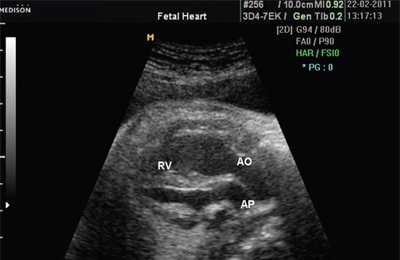

В равной степени это относится к дефекту межжелудочковой перегородки (рис. 6), простой форме транспозиции магистральных сосудов (рис. 7, 8), транспозиции магистральных сосудов с дефектом межжелудочковой перегородки (синдром Тауссиг - Бинга) (рис. 9), общему желудочку (рис. 10), общему артериальному стволу (рис. 10), двойному отхождению сосудов от одного из желудочков сердца (рис. 11).

Рис. 7. Транспозиция магистральных сосудов.

Рис. 8. Транспозиция магистральных сосудов, стрелками показаны ветви легочной артерии.

Рис. 9. Синдром Тауссиг - Бинга. Легочная артерия (отмечена стрелкой) расположена над дефектом межжелудочковой перегородки.

Рис. 10. Общий желудочек с отхождением TRUNCUS ARTERIOSUS. Стрелками показано разделение TRUNCUS ARTERIOSUS на аорту и ствол легочной артерии.

LV и RV - левый и правый желудочек, АР - легочная артерия, АО - аорта, VSD - дефект межжелудочковой перегородки.